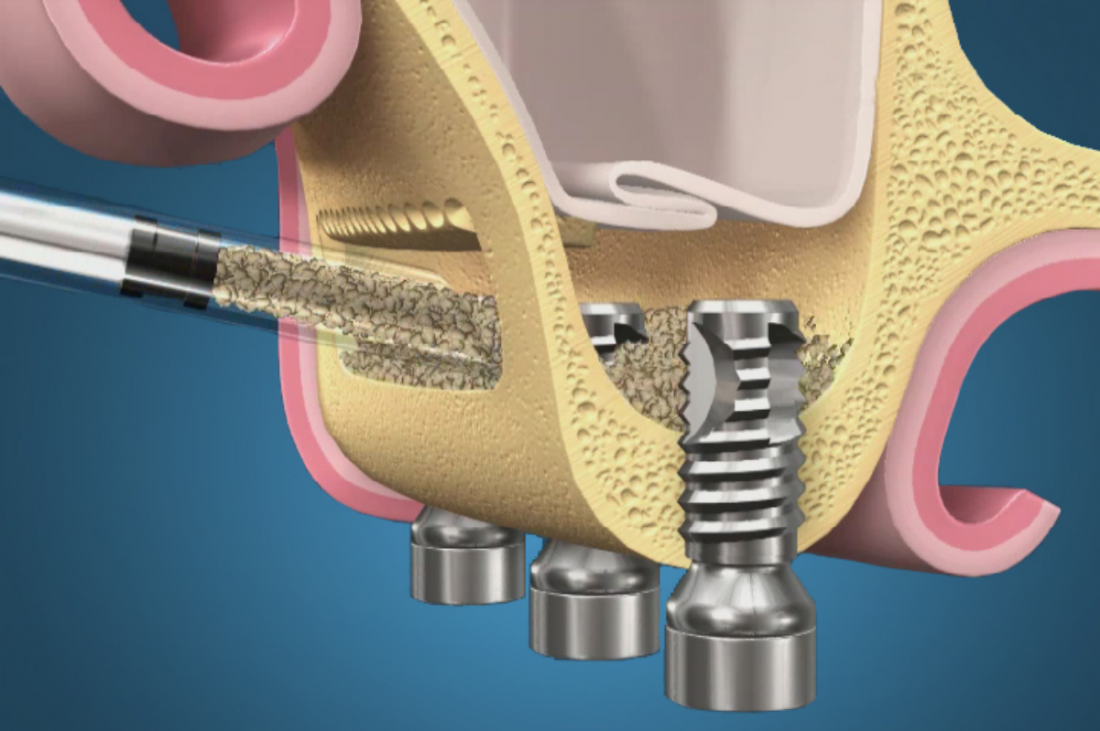

Распространено ошибочное мнение, что синуслифтинг – это операция в гайморовой пазухе. На деле, она проводится не «в», а «под» ней, что также следует из названия (рис. 1,2).

Рисунок 1, 2. Синуслифтинг – операция не «в-», а «под» гайморовой пазухой.